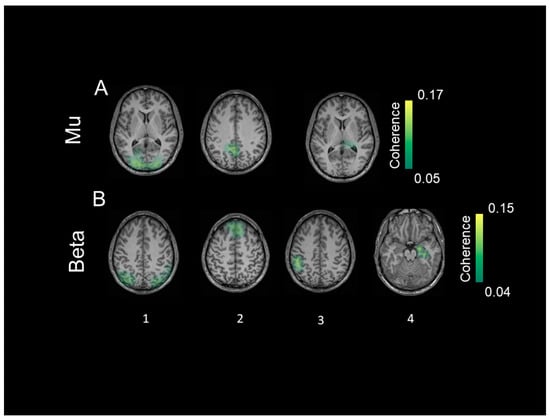

3.4. Coherent Sources

4.3. Coherent Sources